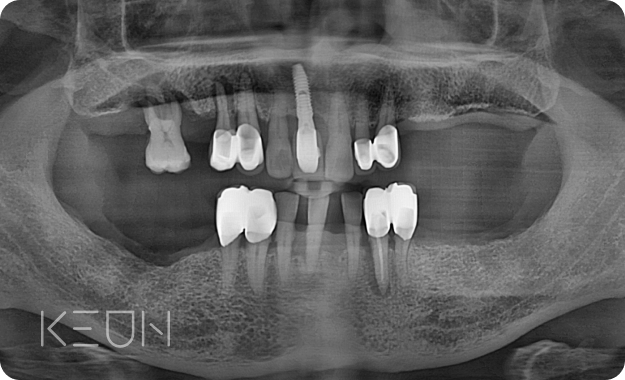

어르신 복합치료 전후사진.

- Before

- After